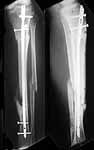

This is a pleasant 23 year old 375lb+ schizophrenic male with a seizure disorder, non-smoker, who had an open tibia fracture in December 2002, complicated by infection and treated(apparently) by multiple debridements (organism unknown). He is not sure specifically where this was done other than "Down south," which on Long Island means west of the Hudson River. He currently resides in an automobile parked near the hospital, where he was admitted last week because of fevers to 103f and a "warm leg" with no other apparent source. He was placed on ancef by the medical service, who admitted him without xrays and only today called an ortho consult.

Wounds are well healed. There are no signs of drainage, and the medial skin graft looks good. He is bearing full weight without pain.

We see cases like this several times a year - always tough to know what to do. I'd recommend getting oblique x-rays and measuring ESR and CRP levels. Based on the xrays that you provided, and his lack of pain, I'd suggest that you could go ahead and remove the rod and ream the canal. Obviously, you'd send a lot of cultures, and I'd give him Vanco to cover MRSA or coag-neg staph. Regarding beads, I usually use PMMA beads and remove them (with a second reaming) after a couple weeks. We used the Osteoset beads for a while, but I didn't like the way that they handled. If you think that he needed continued protection, you could replace the nail at that time. In cases of gross infection and an ununited fracture, I have put some beads inside the second nail. If he seems solidly united, removing the nail and reaming often works, including a 6 weeks course of antibiotic therapy.

The plain films appear to show a healed fracture, but the broken proximal locking screw raises the specter of a nonunion. The pain free weight-bearing's a good sign. Maybe he broke the locking screw months ago and went on to unite?

His radiographs certainly look as though the fracture may be infected. It also may be united. Since there is a titanium rod in place, I would recommend an MRI to look for soft tissue abscesses adjacent to the fracture that may require open drainage. Then removal of the rod with reaming plus/minus intramedullary antibiotic beads (would require later removal). Hopefully the fracture is stable because external fixation in this patient would be a disaster. If the fracture is not stable then I would favor rod removal, reaming and intramedullary antibiotic beads. The beads would require removal or exchange after 3 weeks to minimize difficulty in removal. After at least 6 weeks of IV antibiotics I would ream again and place a new IM rod. He would likely need long term suppressive antibiotics with hopes the fracture will heal and the new rod removed and the infection cleared. Obviously this type of protracted treatment will be extremely difficult to complete in this patient. The planned treatment should minimize the problems encountered by the next poor orthopaedic surgeon whose doorstep he lands on.